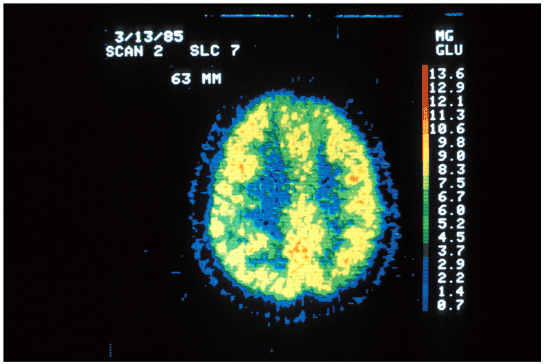

Ak používame iba 10 % nášho mozgu, potom by PET sken mal vyzerať ako nižšie uvedený obrázok. Modrý obrys je lebka a farebný kruh označuje aktívne mozgové štruktúry. Väčšina mozgu by bola tmavá kvôli nečinnosti. (Pozeráte sa dolu na hlavu tejto osoby).

psychologicalscience.org

Ale takto PET sken v skutočnosti nevyzerá. Snímka nižšie zobrazuje skutočný sken zdravého človeka. Celý mozog je neustále aktívny, dokonca aj v obdobiach spánku: reguluje, monitoruje, sníma, interpretuje, usudzuje, plánuje a koná. Dokonca aj ľudia s degeneratívnymi nervovými poruchami, ako je Alzheimerova a Parkinsonova choroba, stále používajú viac ako 10% svojho mozgu.